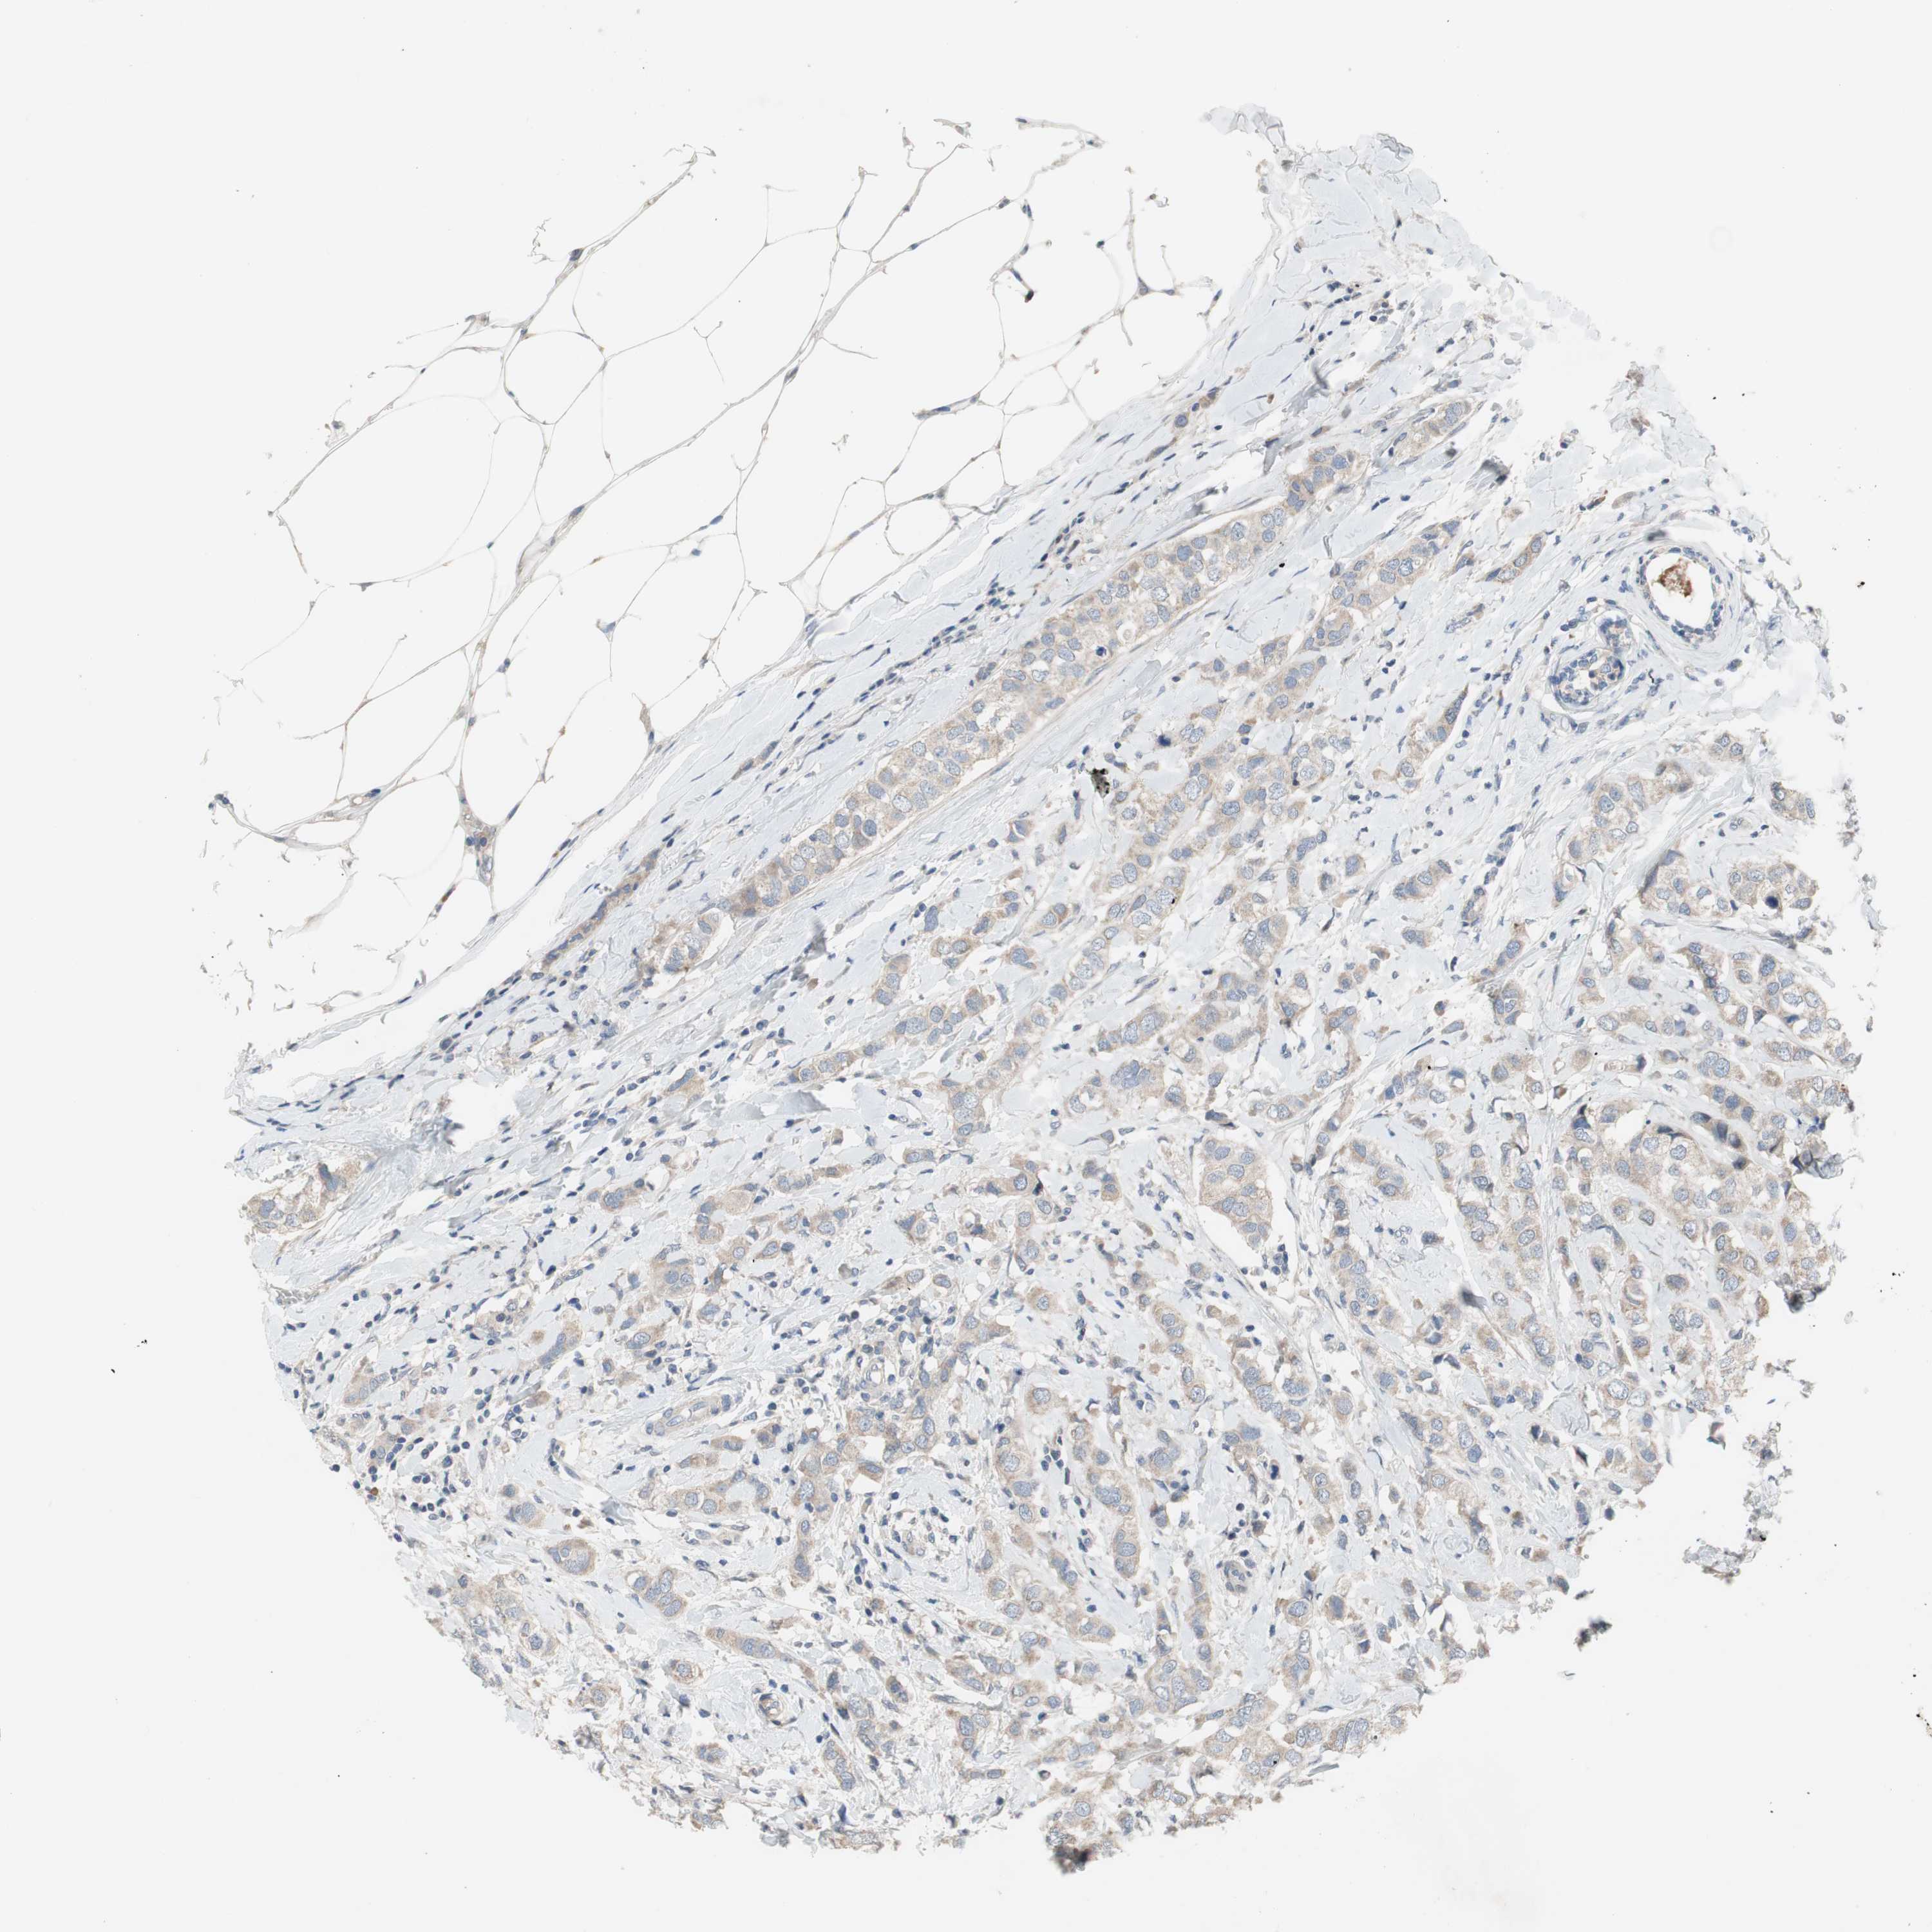

BRCA TCGA BRCA VALIDATION PROTEIN EXPRESSION

ANTIBODIES

AND

VALIDATION